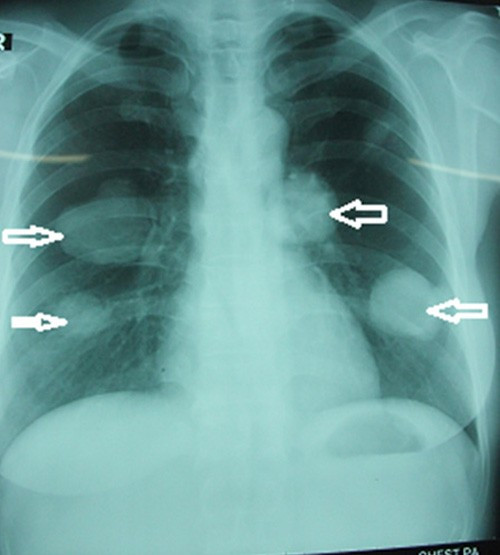

Bệnh nhân nhập viện Lao phổi Trung ương để điều trị, kết quả chụp X-quang cho thấy bệnh nhân có 4 khối u khổng lồ trên phổi.

Đây là trường hợp rất nguy hiểm, bởi mỗi bên phổi bệnh nhân có 2 khối u và không thể phẫu thuật. Nếu cắt sẽ phải cắt toàn bộ phổi và bệnh nhân sẽ tử vong ngay. Các bác sĩ đã chọc dò hút dịch để kiểm tra thì thấy hàng nghìn đầu sán ở mỗi ổ.

Do bệnh nhân không thể phẫu thuật nên được điều trị bằng thuốc, sau 6 tháng uống thuốc chúng tôi kiểm tra thì khối u đã giảm được một nửa.

Loại sán chó chỉ có thể nhìn bằng kính hiển vi, có thể gây tử vong cho người bệnh. Ảnh chụp phổi bệnh nhân là cán bộ y tế bị sán chó làm tổ trong 2 bên phổi.

"Bệnh nhân này là cán bộ y tế, hiện vẫn đi làm bình thường. Tuy nhiên, do vẫn còn ho ra máu, kết quả xét nghiệm vẫn còn sán dây chó, nên bệnh nhân vẫn phải tiếp tục uống thuốc”, tiến sĩ Đề chia sẻ.